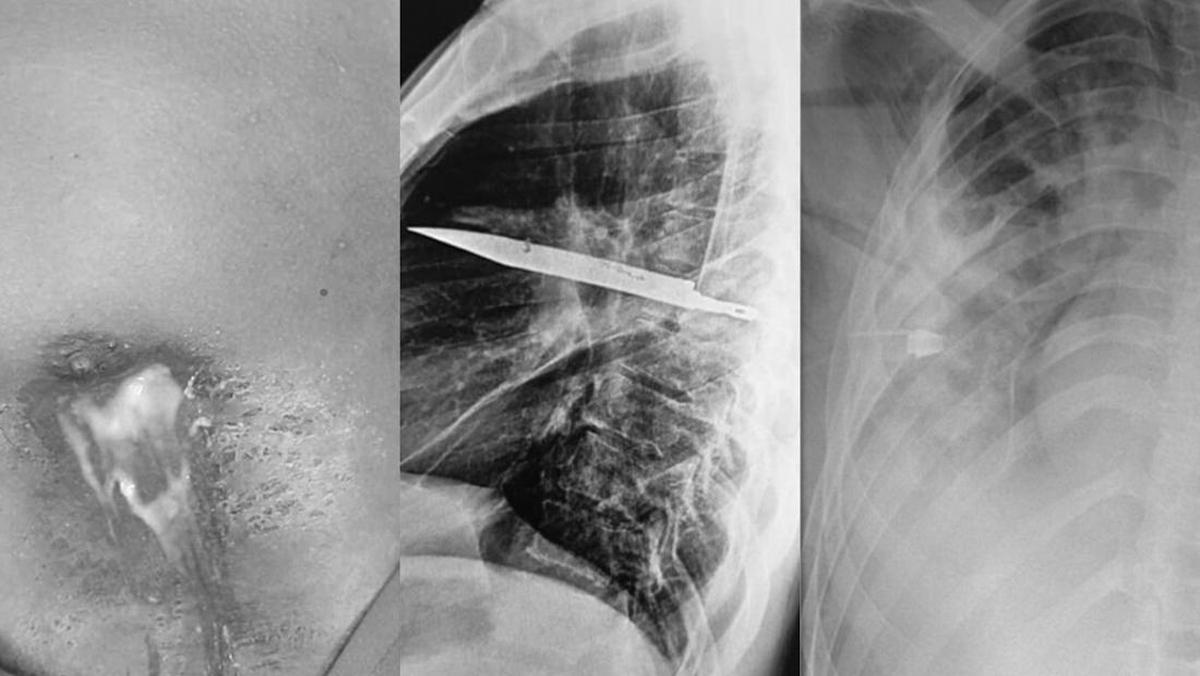

Dokter di Rumah Sakit Nasional Muhimbili, Tanzania, baru-baru ini mempublikasikan sebuah laporan kasus yang sangat tidak biasa di Journal of Surgical Case Reports. Kasus tersebut tentang seorang pria berusia 44 tahun, umumnya sehat, yang datang ke rumah sakit dengan keluhan keluarnya cairan nanah putih dari puting kanannya selama 10 hari. (Foto: Journal of Surgical Case Reports).

Pasien tidak mengalami nyeri dada, sesak napas, batuk, ataupun demam. Namun, ketika ditanya apakah ada riwayat medis yang perlu disampaikan, ia mengingat pernah terlibat dalam perkelahian hebat delapan tahun sebelumnya, yang menyebabkan luka robek di wajah, punggung, dada, dan perut. (Foto: Journal of Surgical Case Reports).

Saat itu, dokter berhasil menutup luka-lukanya dengan jahitan, dan sejak itu ia menjalani kehidupan yang relatif normal, hingga putingnya mulai mengeluarkan nanah. Karena penyebab infeksi tidak jelas, dokter memutuskan melakukan pemeriksaan rontgen. Hasilnya, ada sebuah bilah pisau berukuran besar ternyata tertancap di dalam dada pria tersebut. (Foto: Journal of Surgical Case Reports).